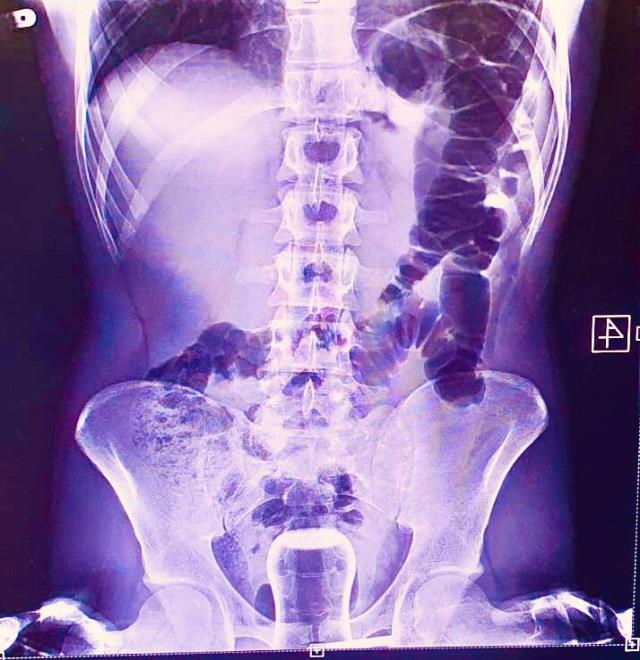

DHA'nın haberine göre; Hacamat tedavisinin ardından 1 hafta geçtikten sonra anüs bölgesinde rahatsızlık hisseden vatandaş, Mehmet Akif İnan Eğitim ve Araştırma Hastanesi'ne başvurdu. Acil serviste hastanın çekilen röntgeninde anüs bölgesinde çay bardağı görüldü. Bu kişi genel cerrahi servisinde ameliyata alındı.

Çay bardağı, uzman doktorlar tarafından gerçekleştirilen operasyonla çıkarıldı. Ameliyatla sancıdan kurtulup eski sağlığına kavuşan hasta doktorlara, uzun zamandır basur hastası olduğunu, hacamatçıya gittiğini ve yağlı çay bardağın kazayla anüs bölgesine kaçtığını ileri sürerek, ameliyattan dolayı teşekkür etti.